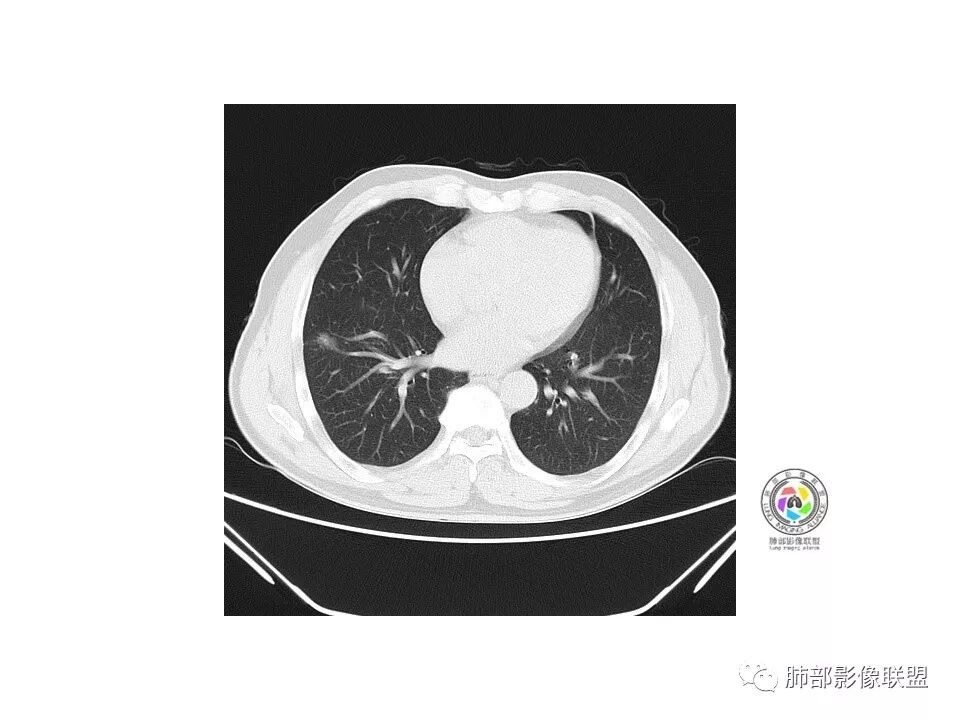

流心明智:

老年男性,咳嗽、咳痰3天。胸部CT:右肺下叶前基底段mGGN,边缘清楚,内可见不规则实性成分,病灶可见空泡、毛刺、胸膜牵拉、血管集束征象。考虑MIA可能大,抗炎2W后复查。

老年男性,右下肺前基底段混合GGN,边缘清晰,月牙铲,叶间胸膜牵拉,有轻度收缩力。结合病史抗炎2-3周后复查,消失考虑炎症,变化不大为腺癌。本例总体支持腺癌

孙冰伟:

老年男性,咳嗽3天,右肺下叶前基底段混合磨玻璃结节,形态不规整,相邻胸膜凹陷,可见血管影,考虑腺癌可能性大,不除外炎症可能,建议抗炎1~2周,1个月复查胸部CT。

红日东升:

右肺下叶mGGN,内部结构紊乱,可见小点状高密度影,边缘清晰,小叶间隔阻挡,轻度收缩力,考虑MIA,常规飞一会20天复查。

生来征服~浪子:

右肺下叶磨玻璃影,边界似清非清(考虑部分为血管断面围绕),周边见条索灶,胸膜牵拉弱。我把炎症放前面,建议抗炎治疗后复查除外恶性。

小赵:

老年男性,右肺下叶前基底段GGN,界清,内部血管结构杂乱,叶间胸膜牵拉。考虑恶性,早期腺癌可能,建议抗炎治疗后复查对比。

张延军:

右肺下叶前基底段见一磨玻璃结节影,呈分叶状,边缘部分模糊,与胸膜间有长条索粘连,内有增粗的血管影,后者边缘毛糙,考虑微浸润性腺癌,建议抗炎治疗后复查

心灵鸡汤:

老年男性,右肺下叶前基底段斜裂旁可见单个混合型磨玻璃结节mGGN,边缘清,内部结构紊乱,进入的血管增粗,支气管关系不好判断,斜裂侧可见牵拉,常规考虑微侵腺癌MIA,建议先抗炎后复查及手术干预。

傅昌瑜:

老年男性,咳嗽咳痰3天。MGGN,边缘见月牙铲、胸膜牵拉,血管移动联通?冠状位隐约可见支气管穿行,考虑MIA,重建冠位可见结节比较靠近叶裂,可积极手术处理。

曹志勇:

老年男性,右S8混合磨玻璃结节,边缘尚清晰,局部凹陷,叶间胸膜牵拉,考虑MIA可能大,建议抗炎治疗10天,6-8周后复查